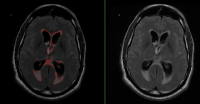

MS Volume

Ventricle Volume

Volumetry of cerebrospinal fluid on Flair